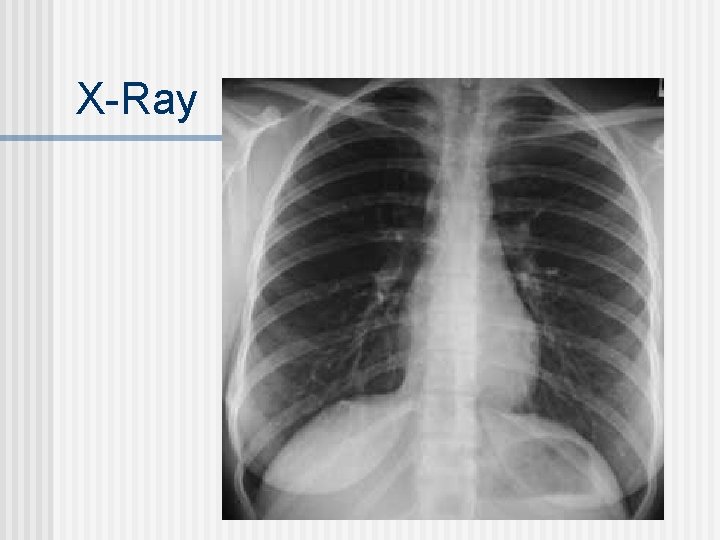

Imaging Procedures X-Rays n MRI: magnetic resonance imaging (no radioisotopes used) - radio waves stimulate H nuclei that give off a signal that can be interpreted for anomalies n PET scans: Positron Emission Tomography n

X-Ray